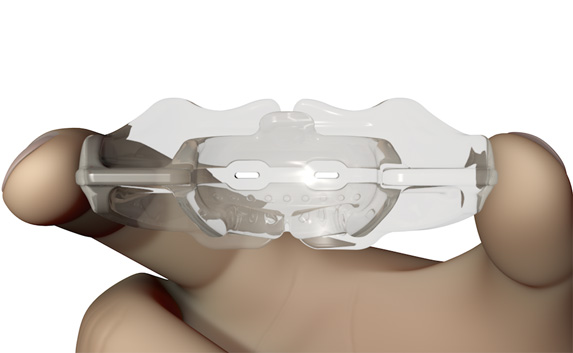

The Myosa® for TMJBDS® S3 is used in the third and final stage of treatment, when the patient's Breath Hold Time (BHT) has reached 45 seconds or more. The S3 is primarily designed to finalise the establishment of nasal breathing, while improving breathing and myofunctional disorders. The S3 can also serve as a transition appliance between the first and second phase of TMJBDS® treatment, involving arch development in combination with the Myobrace® appliances. It is for this reason that the S3 is a derivative of the Myobrace®A1 appliance.